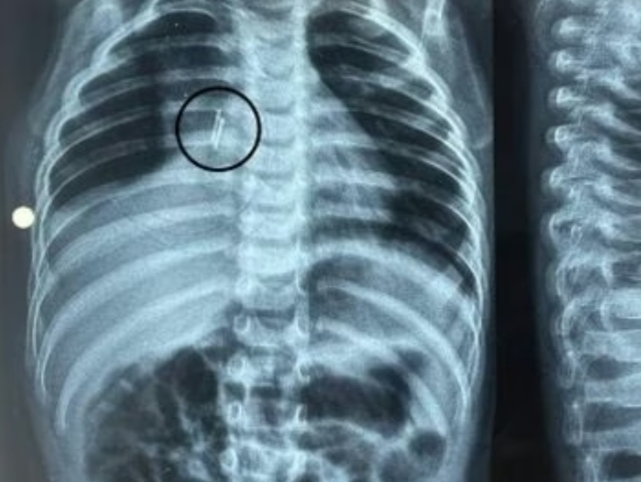

ಚಿಕಿತ್ಸೆಗಳು ವಿಫಲವಾದಾಗ, ಕುಟುಂಬವು ಮಗುವನ್ನು ಗೋತ್ರಿಯಲ್ಲಿರುವ ಸರ್ಕಾರಿ ಆಸ್ಪತ್ರೆಗೆ ಕರೆದೊಯ್ದರು ಅಲ್ಲಿನ ಇಎನ್ಟಿ ತಜ್ಞರು ಪರೀಕ್ಷೆ ನಡೆಸಿದರು ಮತ್ತು ಎಕ್ಸ್ ರೇ ಮಾಡಲಾಯಿತು, ಎಕ್ಸ್-ರೇ ಯಲ್ಲಿ ಶ್ವಾಸನಾಳದಲ್ಲಿ ಸಿಲುಕಿಕೊಂಡಿರುವ ಒಂದು ವಸ್ತುವನ್ನು ಪತ್ತೆಹಚ್ಚಿದರು ಅದನ್ನು ಕೂಲಂಕಷವಾಗಿ ಪರೀಕ್ಷಿಸಿದಾಗ ಸಣ್ಣ ಲೋಹದ ತುಂಡಿನ ಹಾಗೇ ಗೋಚರಿಸಿತು. ಸಂಪೂರ್ಣ ಪರೀಕ್ಷೆ ಮಾಡಿದ ನಂತರ,ಮಗುವಿನ ಶ್ವಾಸಕೋಶದಲ್ಲಿ ಒಂದು ಸೆಂಟಿಮೀಟರ್ ಉದ್ದದ ಎಲ್ಇಡಿ ಬಲ್ಬ್ ಇರುವುದು ಕಂಡುಬಂದಿತು.

ಕೂಡಲೇ ಡಾ.ಹಿರೇನ್ ಸೋನಿ ಮತ್ತು ವೈದ್ಯರ ತಂಡ ಆಧುನಿಕ ಉಪಕರಣದ ಸಹಾಯದಿಂದ ಆಪ್ಟಿಕಲ್ ಬ್ರಾಂಕೋಸ್ಕೋಪಿ ಮಾಡಿ ಶ್ವಾಸನಾಳದ ಕೊಳವೆಯೊಳಗೆ ಆಳವಾಗಿ ಸಿಲುಕಿಕೊಂಡಿದ್ದ ಒಂದು ಸೆಂಟಿಮೀಟರ್ ಉದ್ದದ ಬಲ್ಬ್ ನ್ನು ಶಸ್ತ್ರಚಿಕಿತ್ಸೆ ಮೂಲಕ ಯಶಸ್ವಿಯಾಗಿ ತೆಗೆದು ಹಾಕಲಾಯಿತು ವಿಳಂಬದಿಂದಾಗಿ ಬಲ್ಬಿನ ಮೇಲೆ ಚರ್ಮ ಬೆಳೆದಿತ್ತು, ಶಸ್ತ್ರಚಿಕಿತ್ಸೆಯ ನಂತರ ಮಗುವಿನ ಸ್ಥಿತಿ ಸುಧಾರಿಸಿದೆ ಮತ್ತು ಅವನು ಪ್ರಸ್ತುತ ಆರೋಗ್ಯವಾಗಿದ್ದಾನೆ ಎಂದು ಡಾ. ಹಿರೇನ್ ಸೋನಿ ಹೇಳಿದರು.